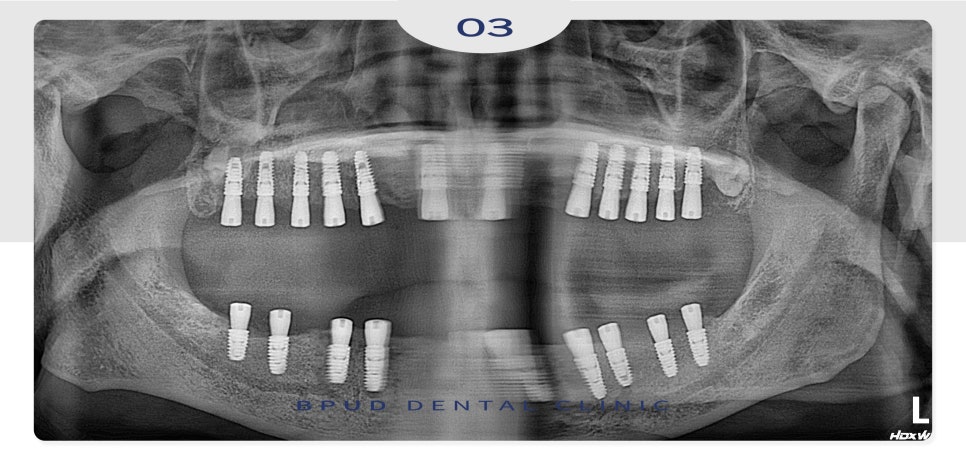

식립할 개수가 많다 보니

위쪽 먼저 식립하고 일주일 뒤

아래쪽을 진행하였는데요.

23.06.12

아래쪽까지 식립을 마친 후에는

잇몸뼈와 인공치근이 단단하게

융합되는 기간으로

약 4~5개월 동안 임시틀니를

제작하여 사용하실 수 있도록 하였습니다.

24.01.23